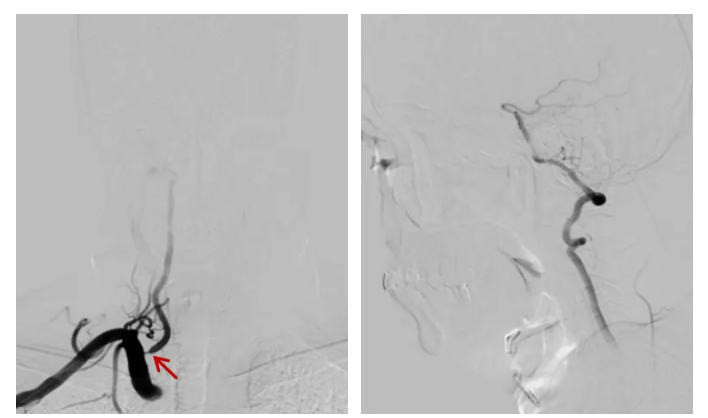

脑血管造影(DSA)示:右侧椎动脉开口局部斑块形成伴狭窄 80%,V4 段局部斑块形成;左侧椎动脉开口处局部斑块形成伴狭窄 60%,左椎偏劣势,主供左侧小脑下后动脉。

神经内科介入团队分析后发现,患者右侧椎动脉开口位置较低。若采用常规方法,支架放置时容易移位,结合导引导管控制支架「半释放技术」可明显减少支架移位的风险。